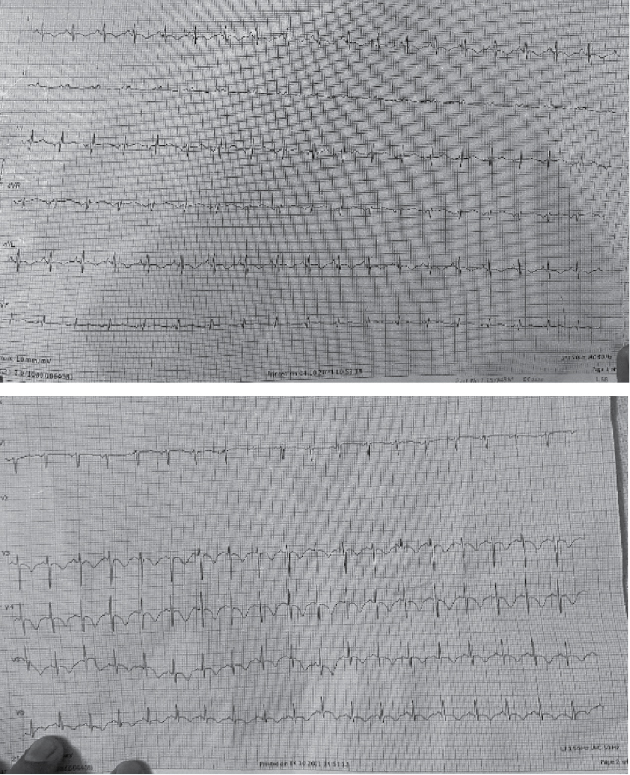

The electrocardiogram (ECG) showed deep and symmetrical T-wave inversion in precordial and lateral leads (Fig. 2). There was an associated elevation of troponin T levels (peak: 432 ng/L), suggestive of myocarditis. Laboratory investigations revealed a normal blood count (Hemoglobin – 13 g/dL, white blood cell [WBC] - 13,200, platelet count - 1,80,000), normal renal (Urea - 36, creatinine - 1.24) and liver function tests (SGOT - 38, SGPT - 45, ALP - 54, total protein - 7.4, albumin - 2.8) and no electrolyte abnormalities.

Figure 2. ECG of the patient.